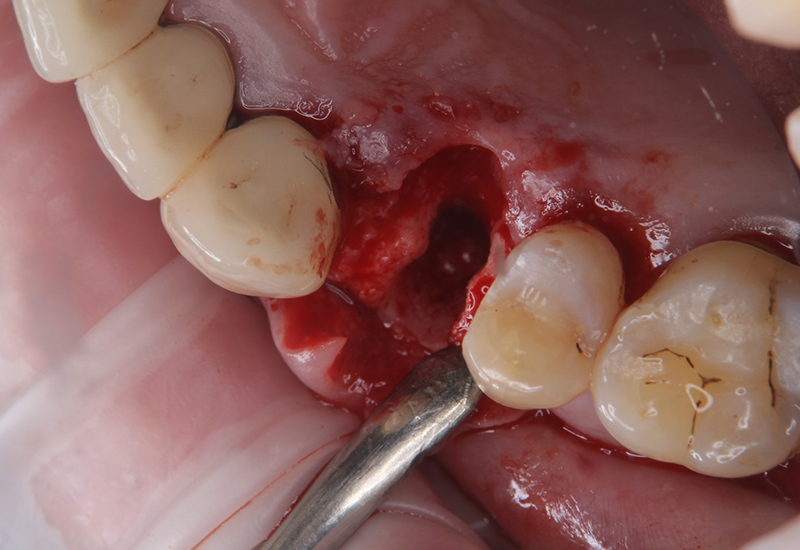

抜歯の画像です